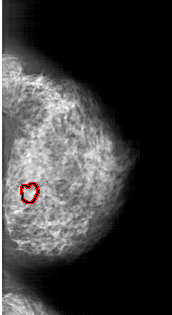

FILE: A_1762_1.RIGHT_MLO.OVERLAY

TOTAL_ABNORMALITIES 1

ABNORMALITY 1

LESION_TYPE CALCIFICATION TYPE PLEOMORPHIC DISTRIBUTION CLUSTERED

ASSESSMENT 4

SUBTLETY 2

PATHOLOGY BENIGN

TOTAL_OUTLINES 1

BOUNDARY